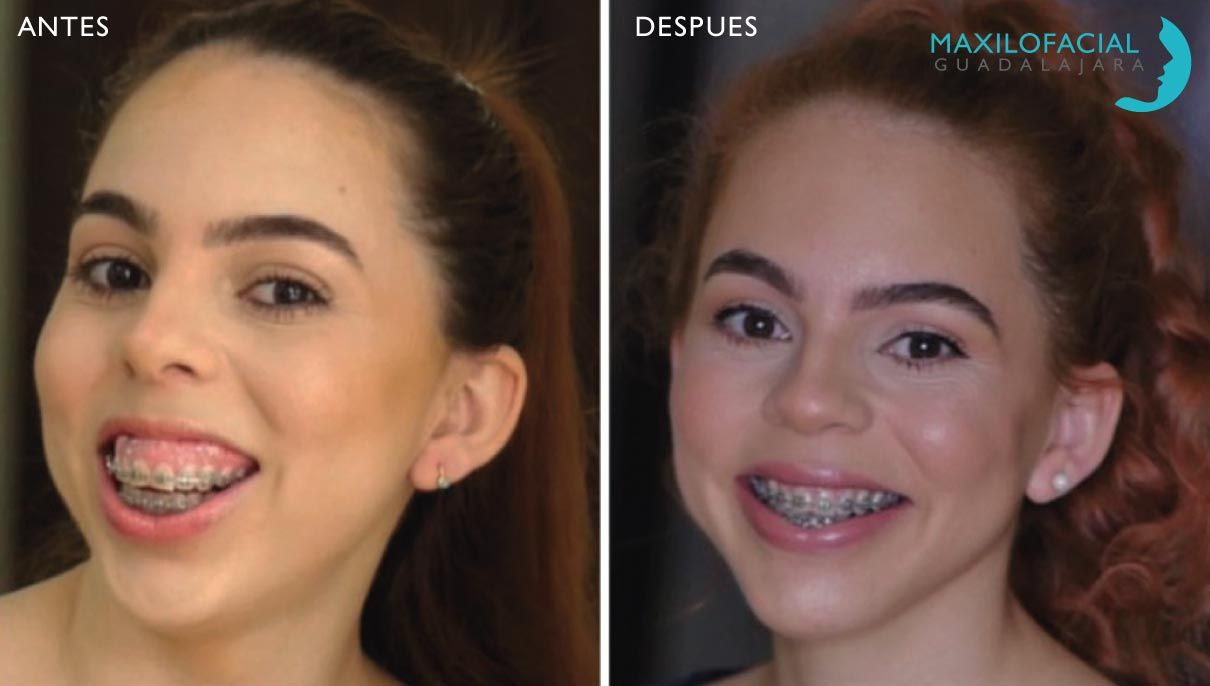

Cirugía Ortognática

Los maxilares son el asiento de los dientes y a la vez la estructura que da la forma a la cara. De ahí la necesidad de compaginar una forma estética del hueso, que conforme una buena estética facial, y a la vez una articulación correcta de los dientes, que permita una oclusión y masticación eficaz. Esta cirugía busca los dos objetivos simultáneamente la estética y la oclusión.

Si tiene una desarmonía facial y sus dientes no encajan perfectamente, consultemos para buscar la mejor forma posible de solucionar ambos problemas.

El tratamiento de estos problemas es combinado cirugía, y ortodoncia.

- Se comienza por una fase ortodoncia alineando los dientes en su lugar en relación con el hueso.

- Posteriormente se movilizan las estructuras óseas hasta su posición ideal que debe compaginar una estética correcta con una oclusión eficaz.

- Finalmente una vez estabilizada la situación ósea se completa afinando la oclusión con ortodoncia pos-quirúrgica.

Cirugía Ortognática

Los maxilares son el asiento de los dientes y a la vez la estructura que da la forma a la cara. De ahí la necesidad de compaginar una forma estética del hueso, que conforme una buena estética facial, y a la vez una articulación correcta de los dientes, que permita una oclusión y masticación eficaz. Esta cirugía busca los dos objetivos simultáneamente la estética y la oclusión.

Si tiene una desarmonía facial y sus dientes no encajan perfectamente, consultemos para buscar la mejor forma posible de solucionar ambos problemas.

El tratamiento de estos problemas es combinado cirugía, y ortodoncia.

- Se comienza por una fase ortodoncia alineando los dientes en su lugar en relación con el hueso.

- Posteriormente se movilizan las estructuras óseas hasta su posición ideal que debe compaginar una estética correcta con una oclusión eficaz.

- Finalmente una vez estabilizada la situación ósea se completa afinando la oclusión con ortodoncia pos-quirúrgica.